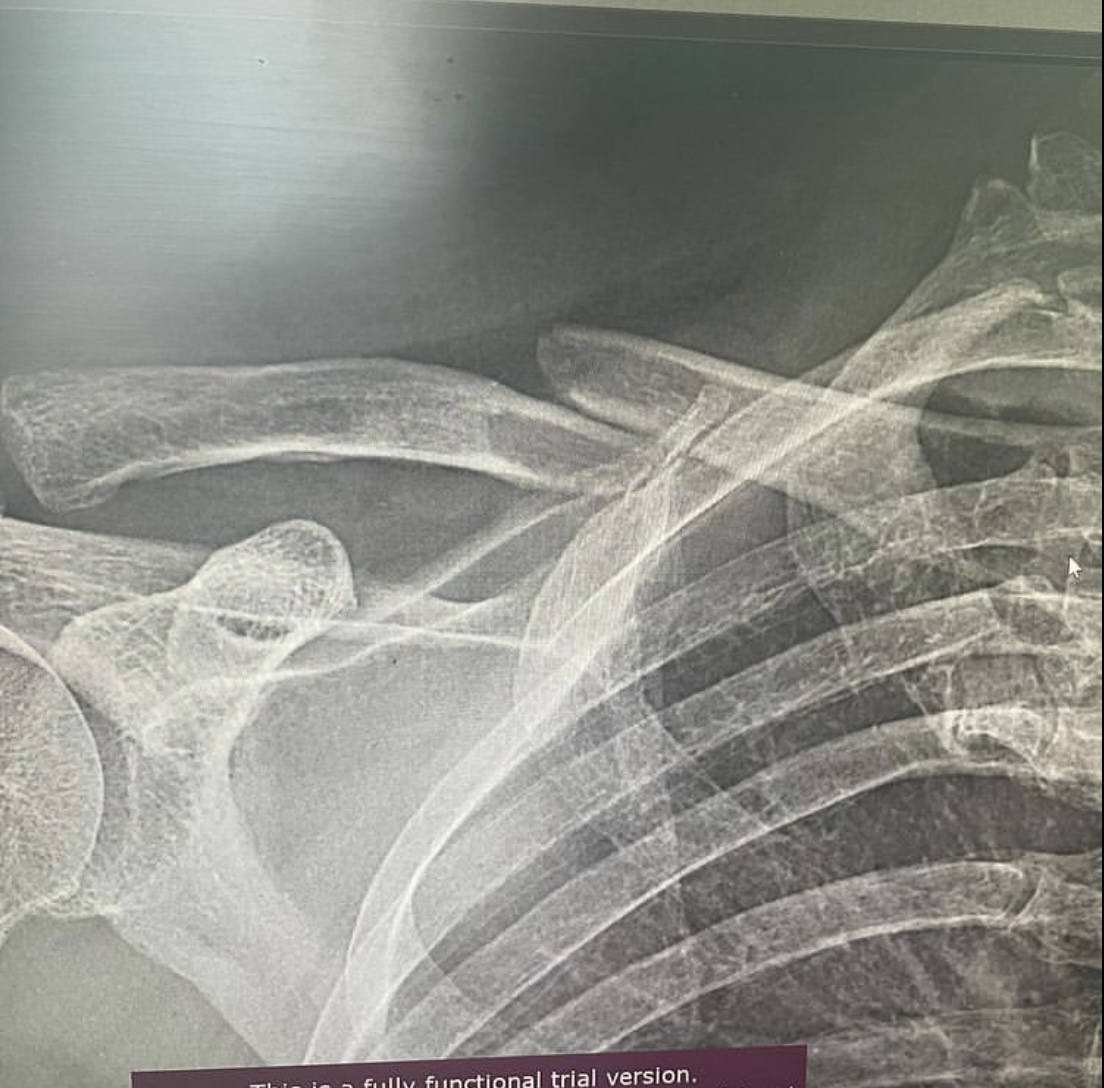

Врач – травматолог – ортопед 7-ой Городской клинической больницы Руслан Ильгизарович Закиров показывает рентген-снимки переломов, которые получили пациенты во время езды на самокате.

Вот снимок мужчины 47 лет, который регулярно пользовался самокатом, поступил в клинику с оскольчатым переломом ключицы. Выполнен остеосинтез пластинной и винтами.